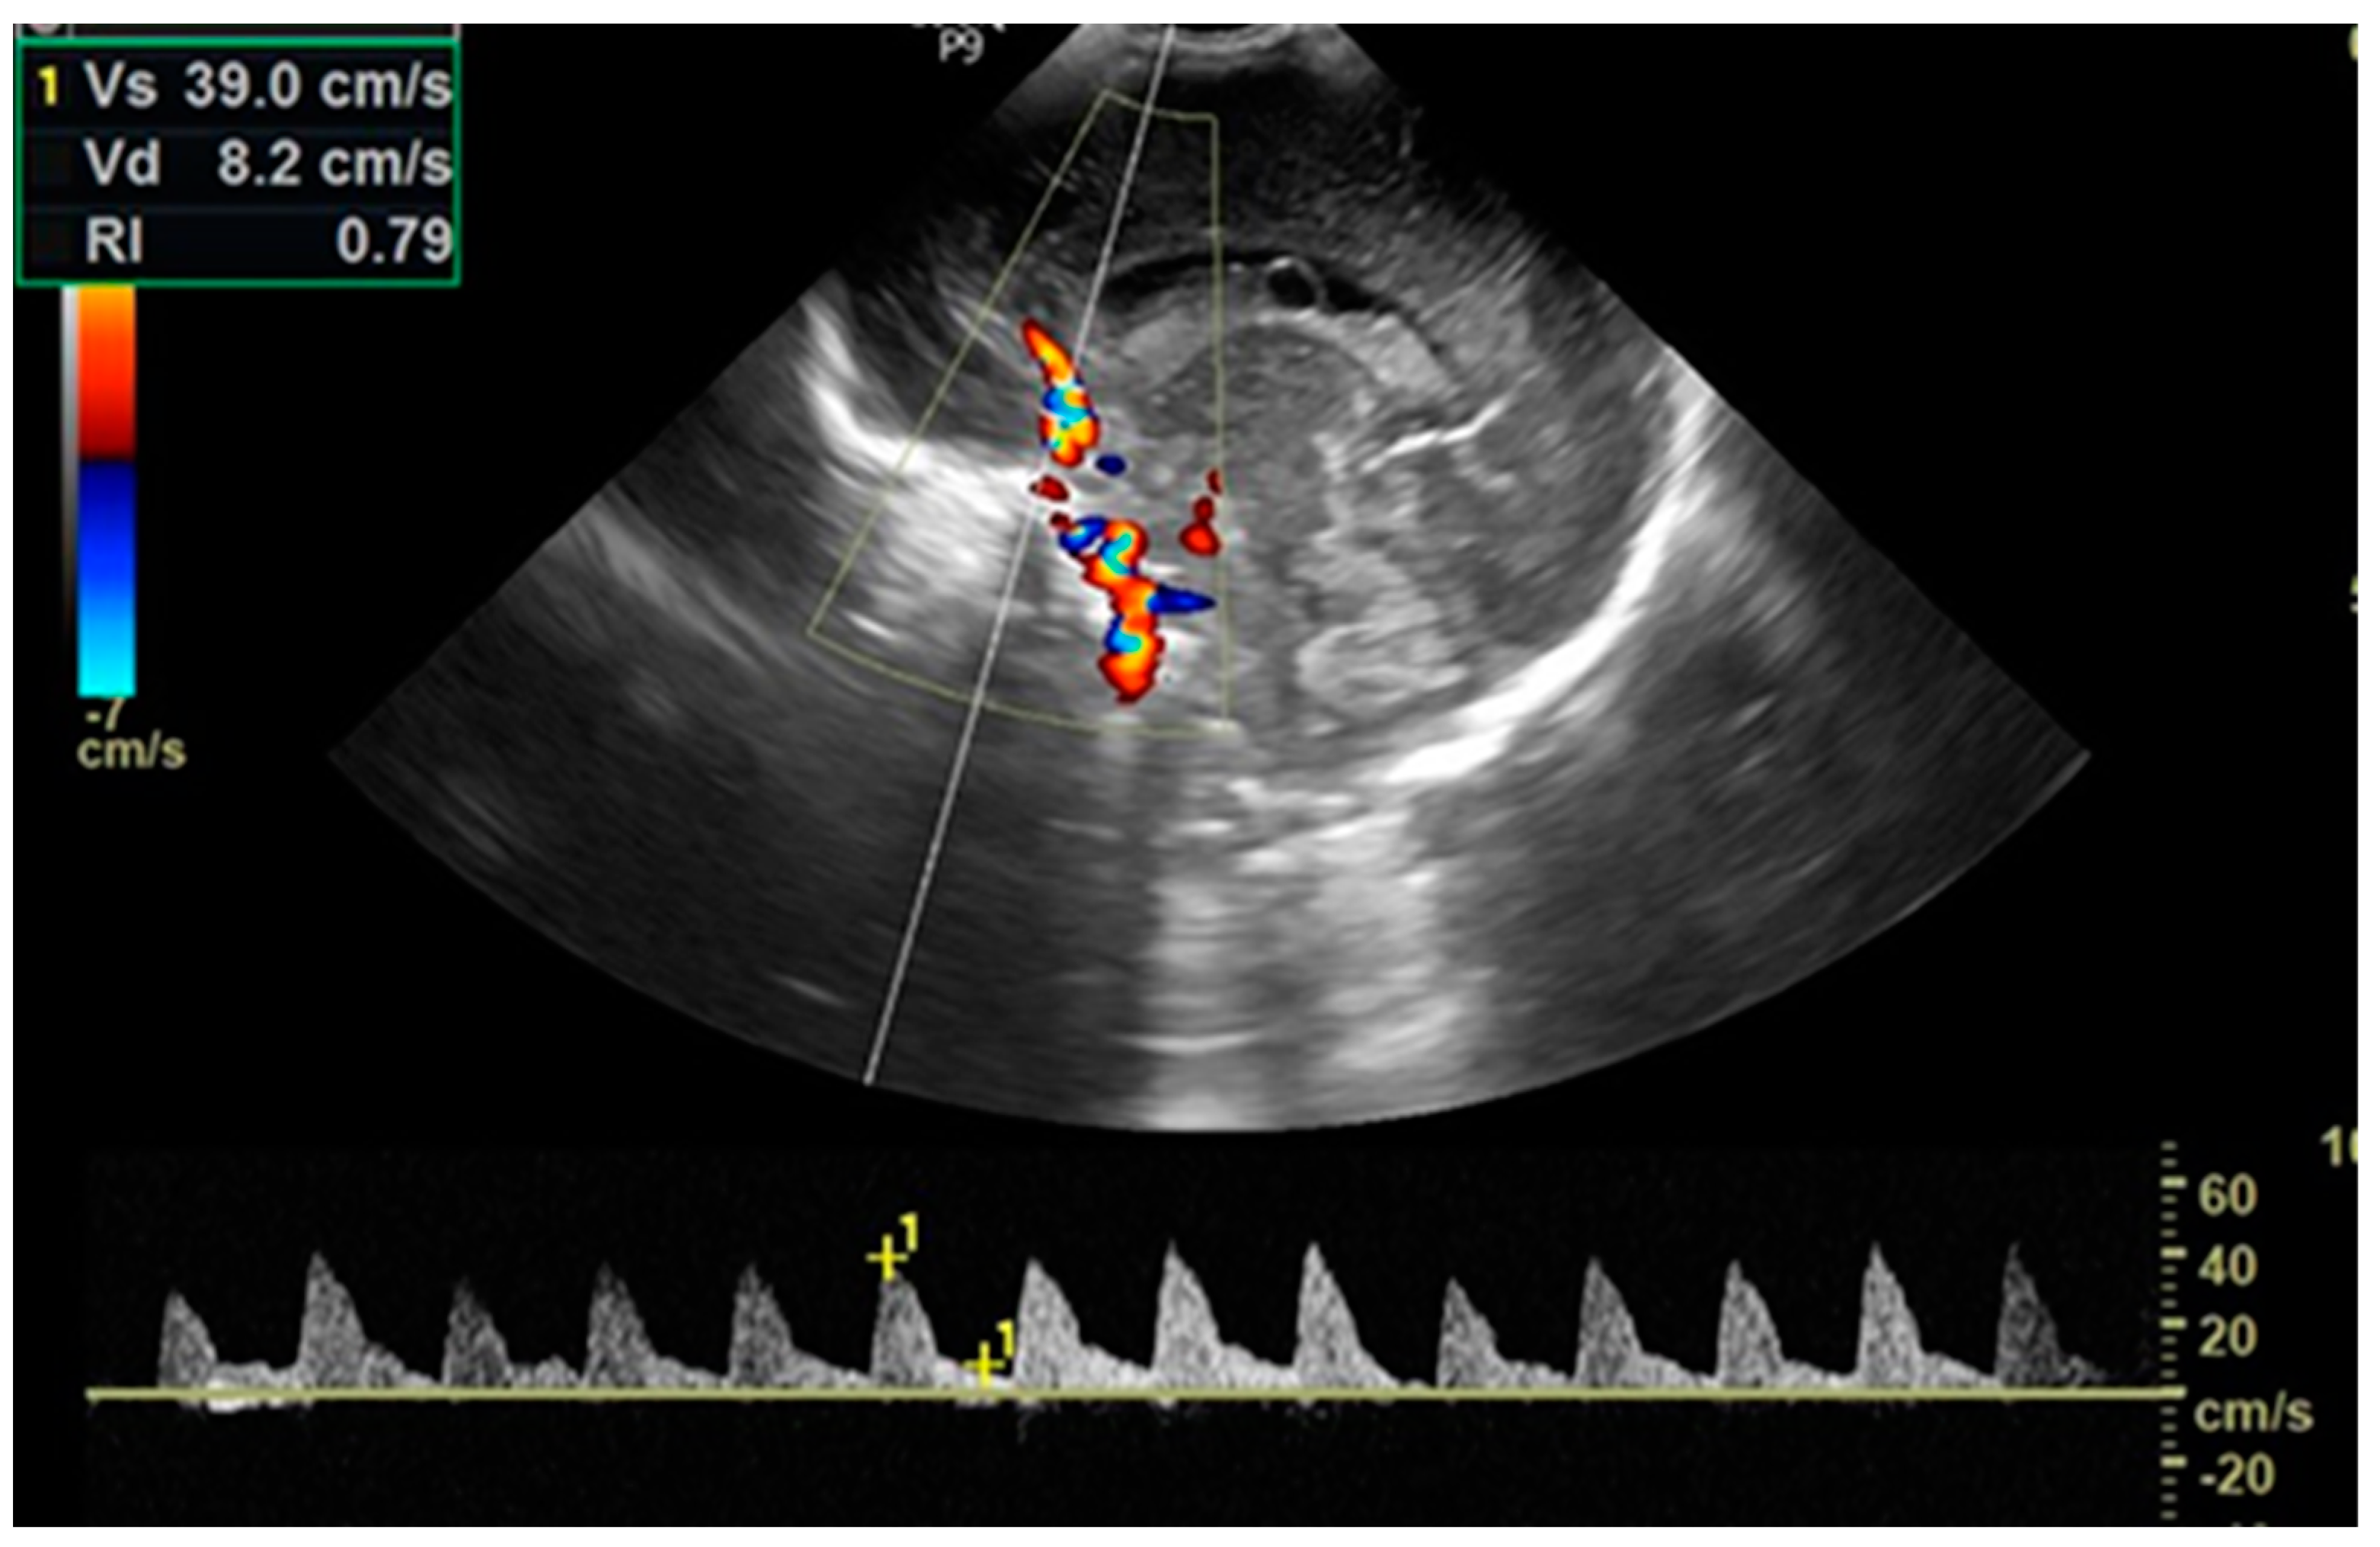

2.5. Cardiac Ultrasounds

| RI §, mean (SD) | ||||||

| within 2 h of life (before PGE1) | 0.718 (0.054) | 0.708 (0.054) | 0.713 (0.05) | 0.3990 | 0.6812 | 0.5761 |

| before BAS | 0.759 (0.046) | |||||

| 24 h of life | 0.769 (0.036) | 0.764 (0.041) | 0.681 (0.046) | 0.6272 | 0.00002 * | 0.00002 * |

| PSV §, (cm/s), mean (SD) | ||||||

| within 2 h of life (before PGE1) | 39.75 (7.41) | 37.78 (7.82) | 34.49 (6.71) | 0.4177 | 0.0007 * | 0.03831 |

| before BAS | 40.41 (8.92) | |||||

| 24 h of life | 38.99 (5.29) | 39.72 (6.53) | 37.35 (7.80) | 0.8958 | 0.5651 | 0.2313 |

| EDV §, (cm/s), mean (SD) | ||||||

| within 2 h of life (before PGE1) | 10.71 (1.61) | 10.86 (2.54) | 9.78 (2.01) | 0.7171 | 0.0292 * | 0.0153 * |

| before BAS | 9.27 (1.91) | |||||

| 24 h of life | 8.74 (1.31) | 9.16 (2.00) | 11.83 (2.39) | 0.687 | 0.00001 * | 0.00002 * |